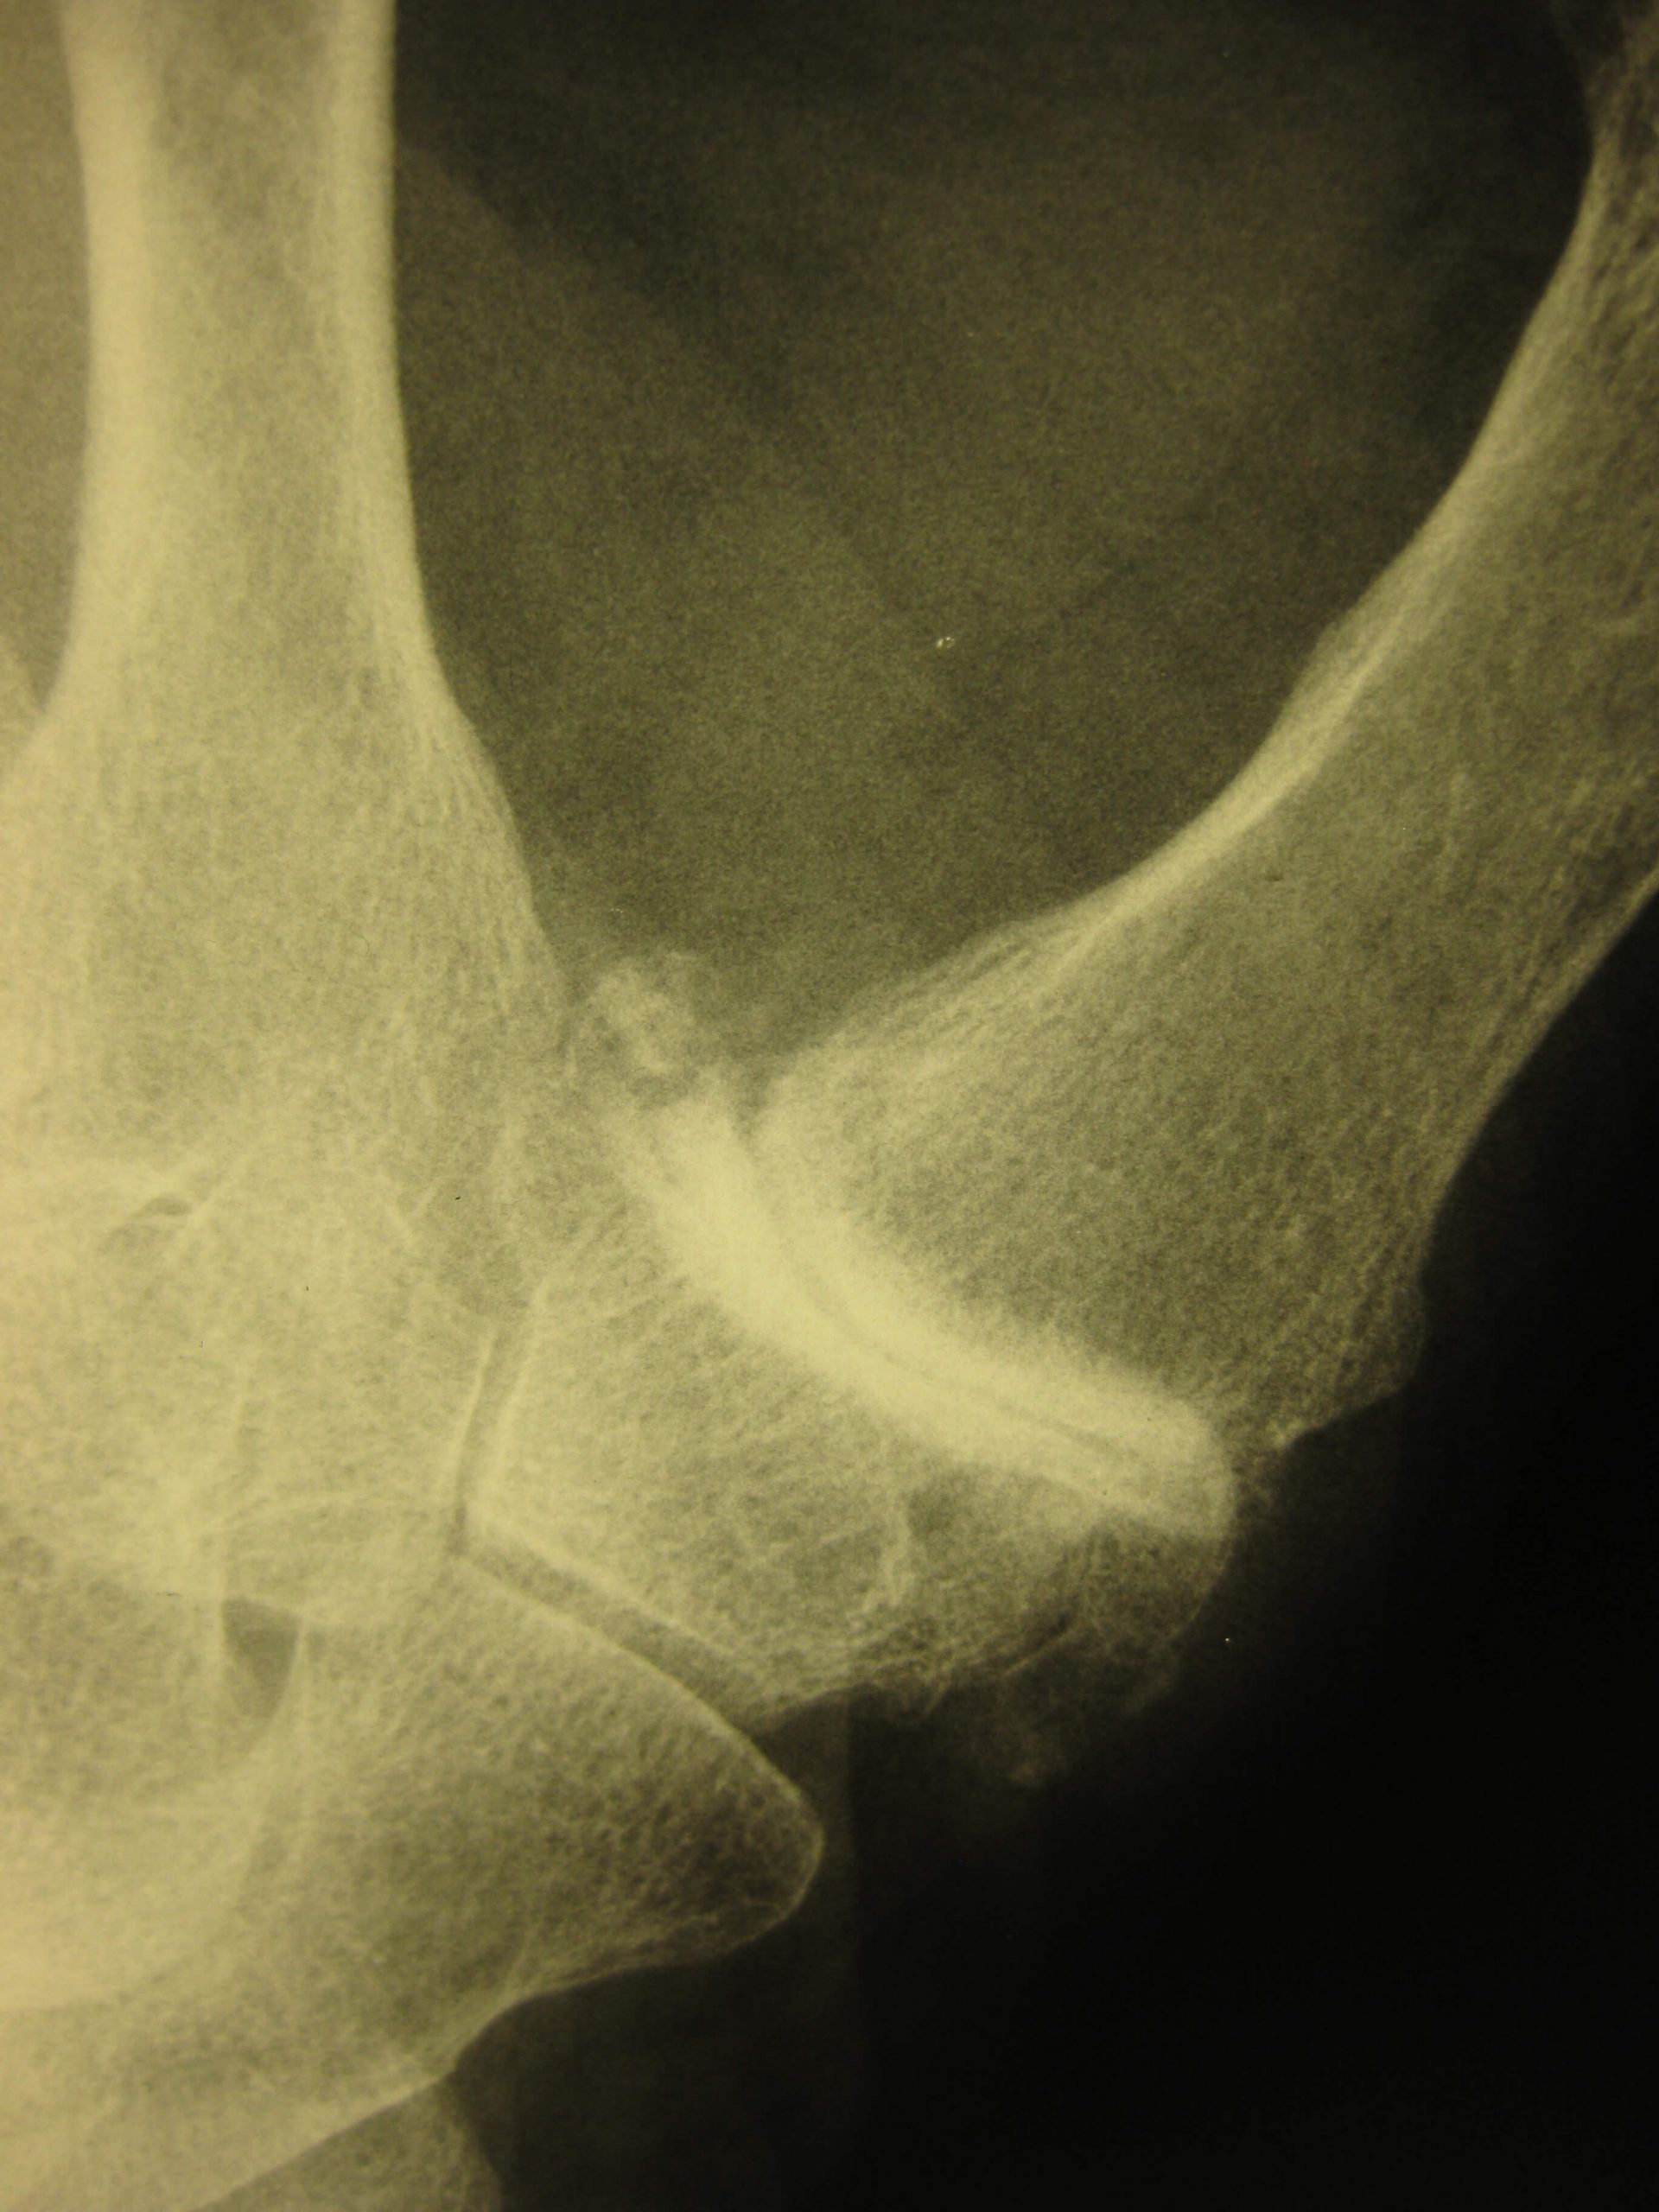

Effettuiamo, tra gli altri, interventi per il trattamento della rizoartrosi con una metodologia chirurgica avanzata che permette la riduzione del dolore, il recupero della stabilità e della forza anche per attività particolarmente pesanti, il mantenimento di un’articolarità del pollice estremamente vicina a quella fisiologica e quindi il ritorno senza limitazioni alle attività lavorative, sportive e di relazione.